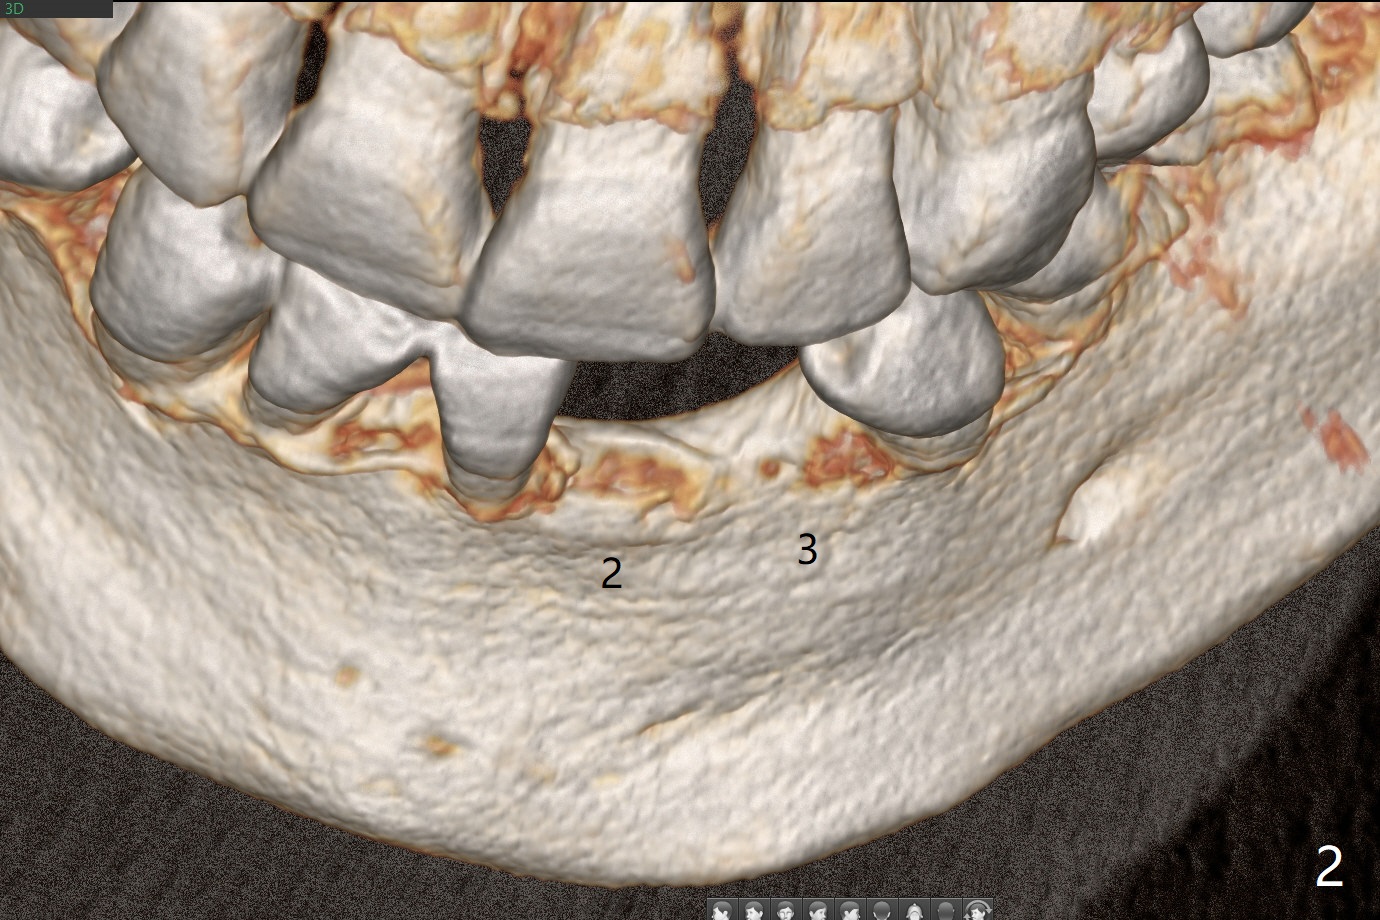

56岁男右下7位点保存一个月,还缺失4个牙齿(图一),左下2,3牙槽嵴特别狭窄,骨皮质为主(图二),应该植入2.0,2.5毫米植体(图三,四),避免复杂植骨术。而右上3骨质也狭窄,但是骨质密度低,几乎松质骨(图五),如果采纳骨膨胀术(高速倒转),植体可以大于4.0毫米,防止植体断裂。左上7骨质宽,但是短,5x8.5毫米植体可能胜任功能(图六)。如果植入10毫米植体,需要做上颌窦提升。